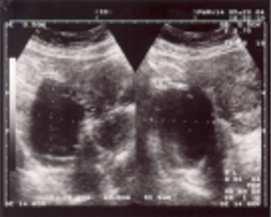

詳解

破題關鍵

這題的解題核心在於辨識影像中「脂肪」和「鈣化」的特徵,這兩者是卵巢畸胎瘤最典型的影像學表現。

選項拆解